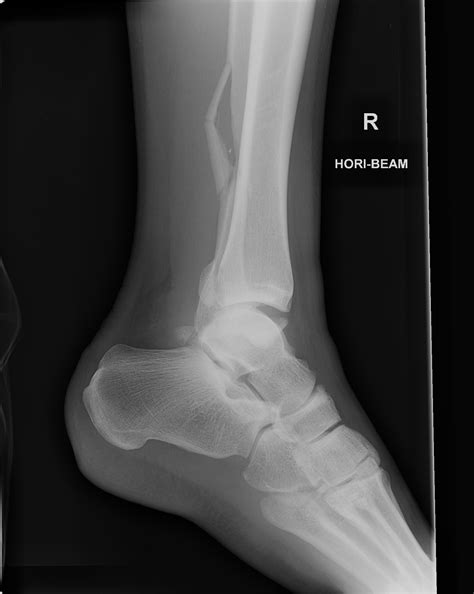

Lateral View Shows the side of the foot, providing a profile view of the bones and joints.

• normal foot x ray series